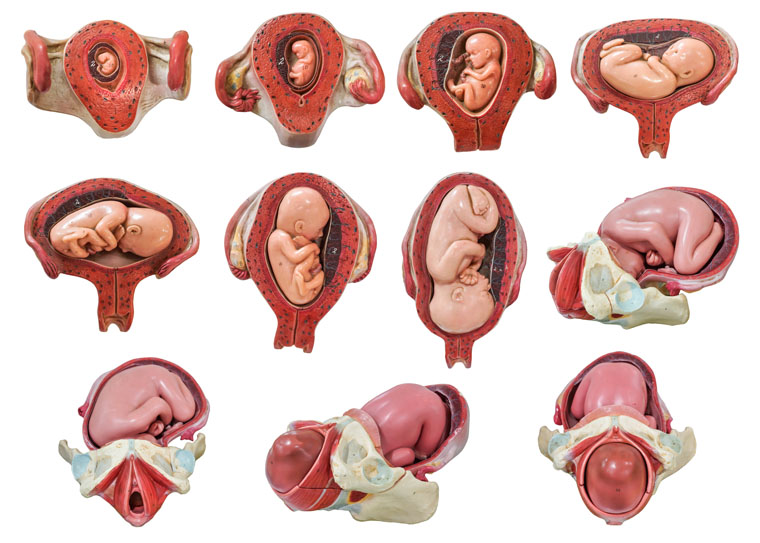

Fosterutvikling i livmoren

Utviklingen av et menneske fra befruktning til fødsel :